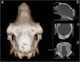

Trepanning, also known as trepanation, trephination, trephining or making a burr hole (the verb trepan derives from Old French from Medieval Latin trepanum from Greek trypanon, literally "borer, auger") is a surgical intervention in which a hole is drilled or scraped into the human skull. The intentional perforation of the cranium exposes the dura mater to treat health problems related to intracranial diseases or release pressured blood buildup from an injury. [Source: Wikipedia ]